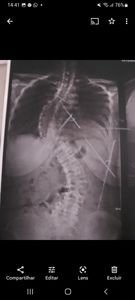

Olá! meu nome é Francinele de Oliveira, moro em Caxias - MA, tenho 48 anos e venho pedir uma ajuda. No início de 2018, fiz uma cirurgia de retirada de um Meningioma, tumor benigno, e devido a essa cirurgia fiquei com os movimentos da perna direita comprometidos.E em novembro de 2021, fiz uma cirurgia na coluna para resolver a escoliose que eu tenho desde criança. Tenho 80 graus na parte torácica, e 60 graus na parte lombar, mas, meu corpo rejeitou essa cirurgia, o que piorou meu estado físico e minha deficiência na perna e agora preciso de ajuda pra realizar um tratamento, no Piauí. O tratamento é a terapia neural, com uma fisioterapeuta, e preciso de fisioterapia mais específica pra minha perna.